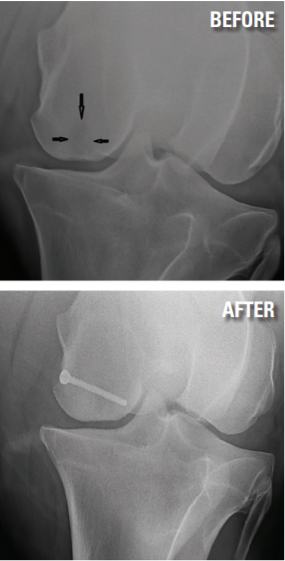

Subchondral bone cysts are lesions within bones adjacent to a joint. They’re often associated with lameness and can be difficult to treat. The medial femoral condyle is part of the stifle joint and is a common site for such lesions. In some cases, we believe that these are developmental, a failure of the bone to correctly develop. More recently, we have identified these lesions as a result of trauma to the bone, which causes inflammation within the bone leading to degeneration.

Many treatment options are available, such as conservative treatment with rest, injection of corticosteroid into the cyst, surgical debridement and, more recently, packing of the cyst with regenerative therapies such as bone marrow or stem cells. As in many cases where there are many treatment options, no single therapy has been shown to offer consistent favorable long-term results. Recently, the surgeons at Palm Beach Equine have used a technique described by Dr. Santschi and others in 2015. This surgical technique involves the placement of a screw across the cyst using radiographs as guidance. The idea is that this alters the biomechanical forces through the bone. We’ve seen very good results with this technique, and in time, we hope to see long-term positive results. In April, I performed a follow-up exam on a dressage horse that underwent this procedure in 2016 as a 7-year-old. She returned to training after a couple of months and is now showing successfully and is 100 percent sound.